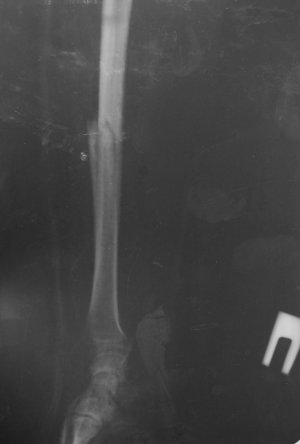

Добрый день. Мне 54г. 28.12.2013 во время неудачного ограбления (грабили меня) получил перелом правой руки, со смещением. Доктор говорит, что пока операцию с наложением пластины делать не стоит, может срастется нормально. Но я работаю за компьютером...и что то рука болит с опуханием периодически...и последний снимок мне абсалютно не нравиться...что то мне все грустнее и грустнее. Вопрос: может мне настоять на операции? Мне очень нужна полноценная правая рука.. Фотосесию флюорограм предоставлю. Помогите пожалуйста добрым совет